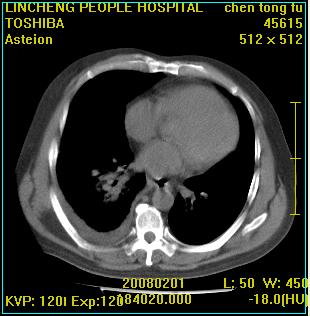

患者,男性,62岁。主因头晕,发热,咳嗽6天,高热达39度,esr19mm/h,wbc 3.9×10 9/l

实变区见空气支气管征,支气管通畅,考虑为大叶性肺炎,右侧少量胸水

实变区见空气支气管征,支气管通畅,考虑为大叶性肺炎,右侧少量胸水。